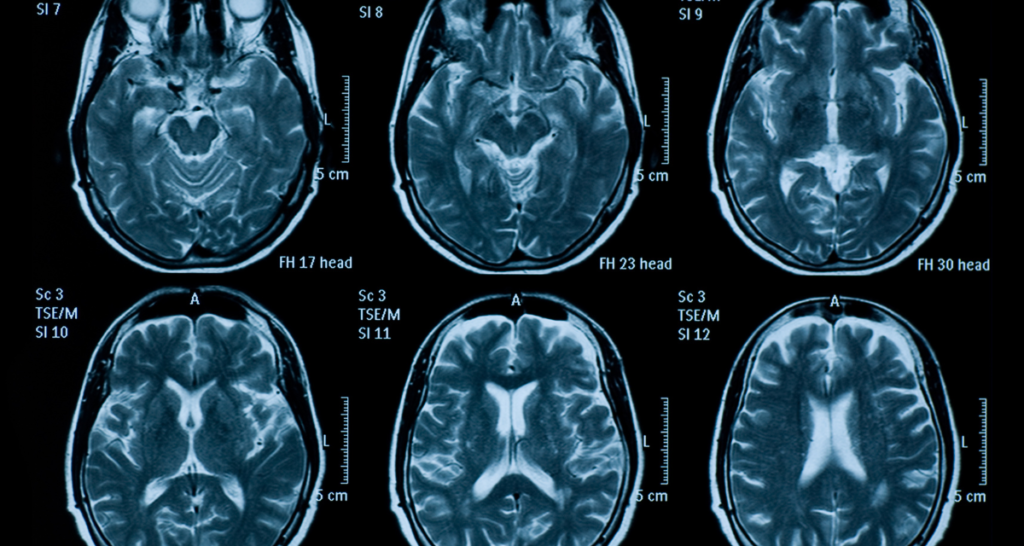

Brain MRI

A brain MRI may mention white matter, ventricles, and structures like the cerebellum or brainstem. Mild white matter changes can be age related and are very common after age 40.